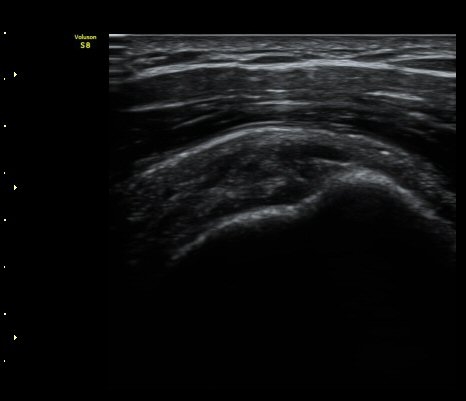

ÀÌµÎ¹Ú±Ù°Ç È¾´Ü¸é°Ë»ç¿¡¼­ ƯÀÌ ¼Ò°ß ¾øÀ½

(no specific abnormal findngs with transverse scan of biceps tendon) »çÁø 1, 2